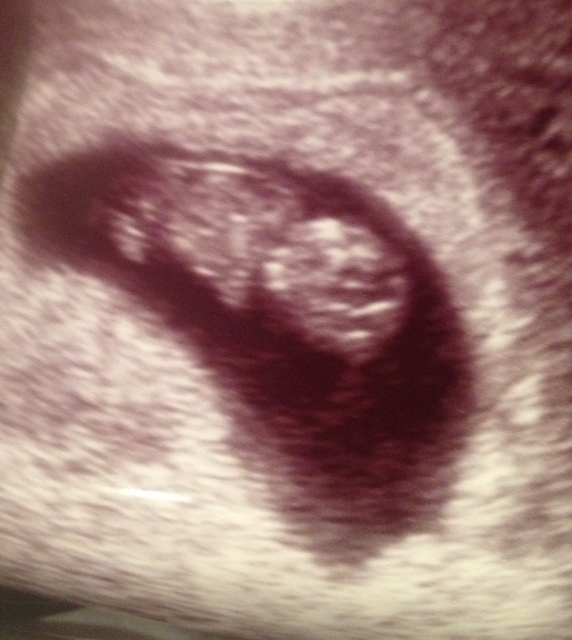

We had our first official prenatal appointment yesterday. It went well. Besides the really long wait to be seen (and therefore pee) I am really glad we chose to go with them. Everyone is so nice and pleasant. We got to see the bug again and it was the first non invasive sono I have had. It was fantastic to not get probed. I was a little worried that my extra fluff would get in the way of a clear pic, but my worry was for nothing because we were able to see the little one bouncing, waving and kicking. The heartbeat was nice and strong and once again all looked well. I have to admit all that pressing hurt like hell and I am still hurting a little today, but it was so worth it. I had some blood taken, although my definition of some differs from their 7 tubes. Then we sat and talked to the PA who was very nice but a little off on her due date wheel. She had us measuring at 11 wks 5 days and we were only 11 wks 3 days but no biggie. Anyway we left there with 3 appointments scheduled. We have our first trimester screening on 2/11, we go back for results on 2/25 and then we go in for our 16 wk (hopefully gender reveal sono) on 3/5. Busy, Busy, Busy and it feels like it is already flying by.

I will leave you with a pic and some stats to tide you over for now:

| the baby bug just chillin' knees up arms bent , sittin' and relaxin'. |

How far along? 11 wks 4 days

How big is baby? the size of a lime